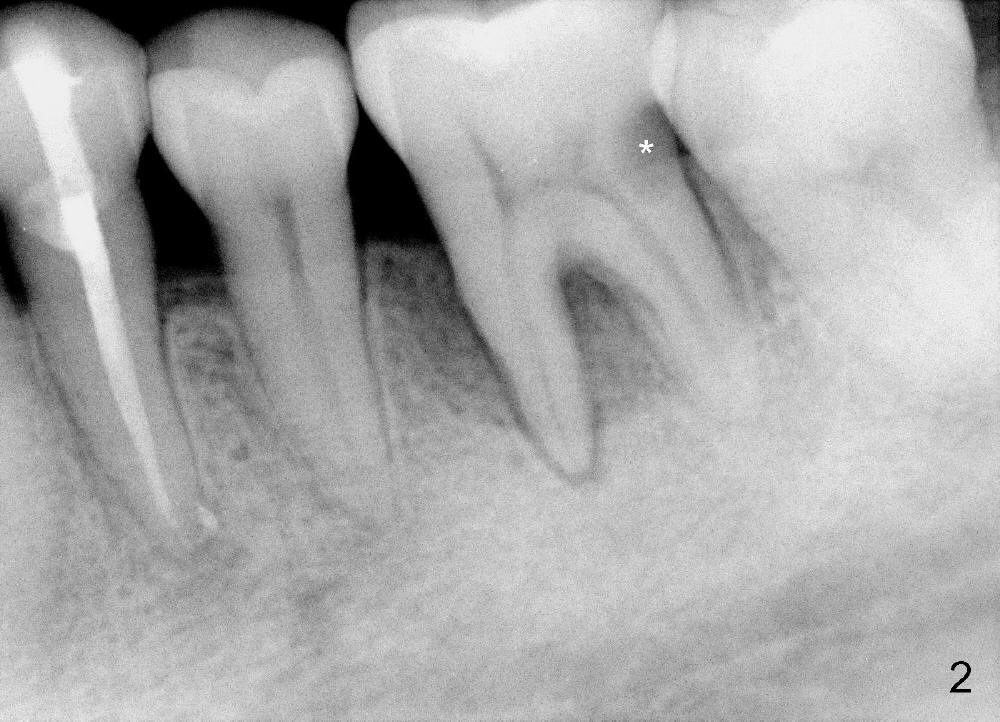

A 48-year-old lady has poor dentition. Four years and a half ago when the tooth #21 needed root canal therapy (RCT), the tooth #19 showed bone loss (Fig.1 arrowheads) and hidden caries (white *). The carious lesion caused severe toothache 2 years later (Fig.2 *), while the perio lesion remain severe. The tooth #19 received RCT; the patient remained asymptomatic until recently. Since the patient is satisfied with immediate implant with the tooth #2 (mainly perio lesion), she is not hesitant in accepting the same mode of treatment for #19.